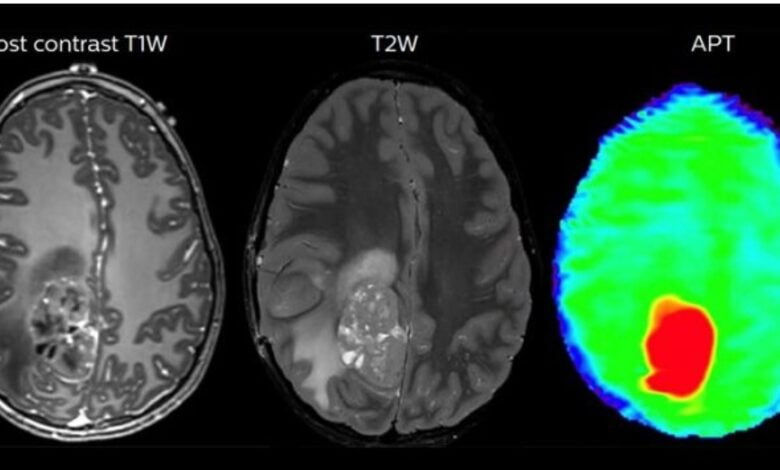

El primer objetivo de este equipo de físicos, médicos, biotecnólogos y matemáticos es atacar con los microrrobots los tumores cerebrales, que son «particularmente difíciles» de tratar con la tecnología actual, ya que la radiación y la cirugía en la cabeza pueden causar daños severos e irreversibles.

Ahí entra el avance científico de Bionaut Labs: ser capaces de administrar medicamentos directamente en el tumor, sin afectar a cualquier otra parte del cerebro.

Para el inicio de su andadura, Shpigelmacher, formado en física, matemáticas, finanzas y ciencias de la computación, y su equipo decidieron enfocarse en el tratamiento de gliomas del tronco encefálico, un tumor pediátrico «incurable».